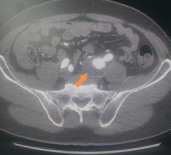

患者在体检中发现左髂动脉瘤,瘤体累及髂总动脉及髂内动脉近段,直径较大,破裂风险高,具备明确手术指征。术前沟通中患者明确表达了对术后性功能的保留。而临床数据显示,传统主髂动脉瘤腔内治疗常因牺牲一侧髂内动脉,导致约30%–60%的男性患者出现血管性阳痿,严重影响生活质量。

术前CTA